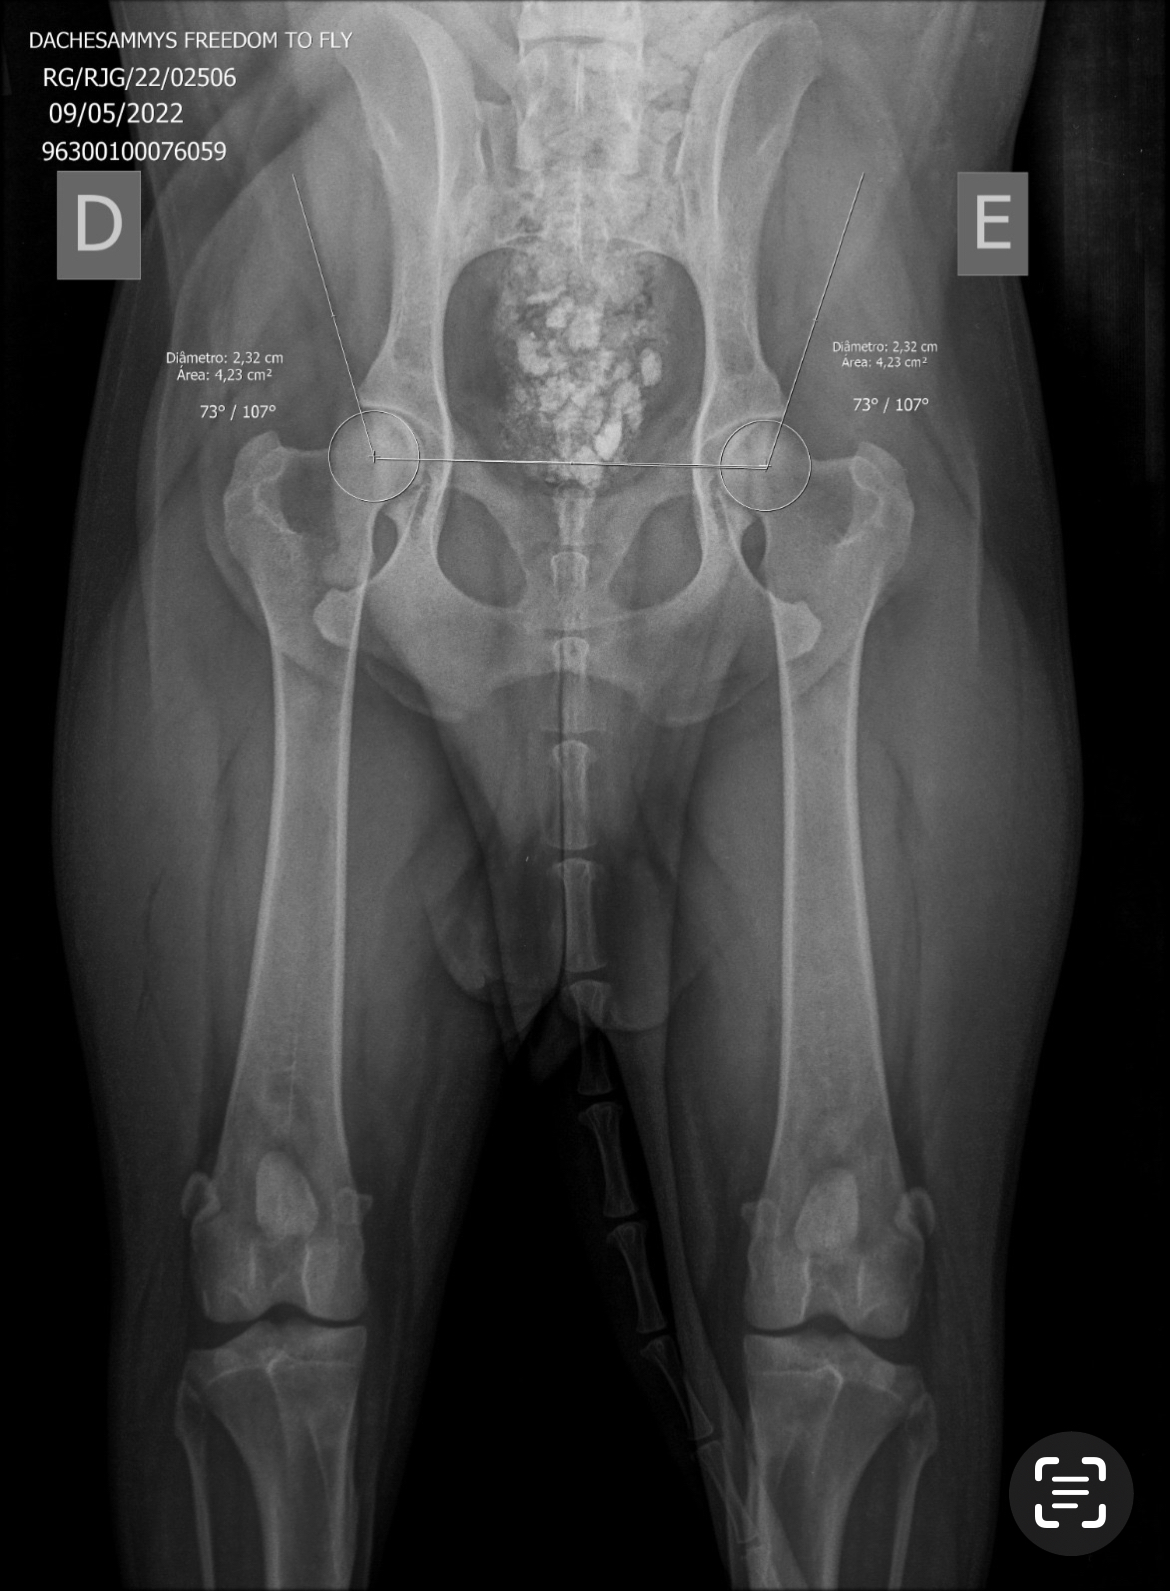

Data Nasc : 09/05/2022

Registro CBKC RG/RJG/22/02506

CHIP NR 963003100076059